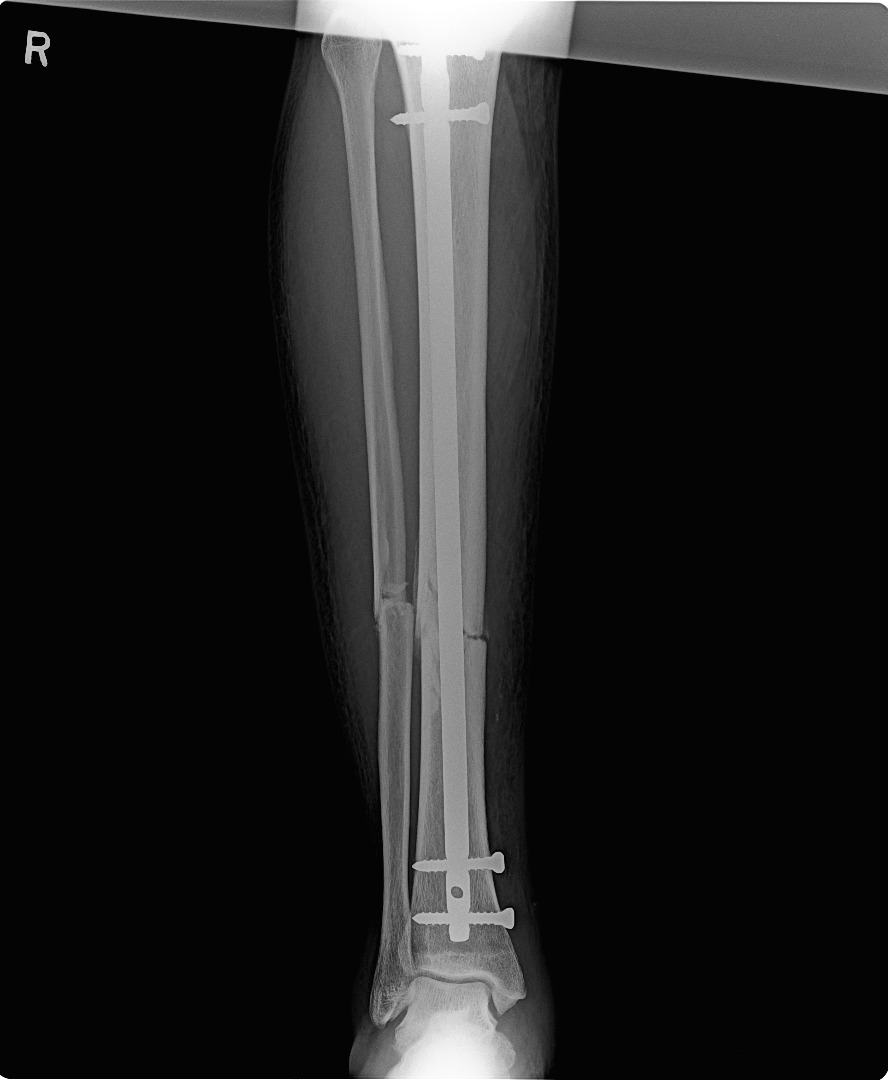

TRAUMA SURGERY & MINIMALLY INVASIVE FRACTURE SURGERY

trauma surgery

minimally invasive fracture surgery